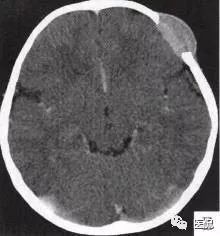

颅脑CT示:图A〜D,CT平扫示左侧额骨、蝶骨见溶骨性骨质缺损,边界清晰,周围无硬化边,伴有软组织肿块向脑外生长,边缘光滑,脑内无明显侵犯;

1.有无病变:病变明确。

2.定位诊断:额骨、蝶骨均可见局限性骨质破坏,穿破颅骨内外板,见软组织肿块突向脑外;肿块与硬脑膜界限清楚,脑实质无侵犯;应考虑颅骨来源,向颅外侵犯。

②颅骨多处溶骨性破坏,穿透颅骨内外板;

③骨破坏无 硬化边,边缘光整,无膨胀;

④软组织肿块形态规则,边缘光滑;⑤脑膜及脑组织无侵犯, 表现为推压或移位。后三点均支持为良性肿块,结合年龄、实验室检查等,诊断不难。本例经病理(图I)证实为:嗜酸性肉芽肿。